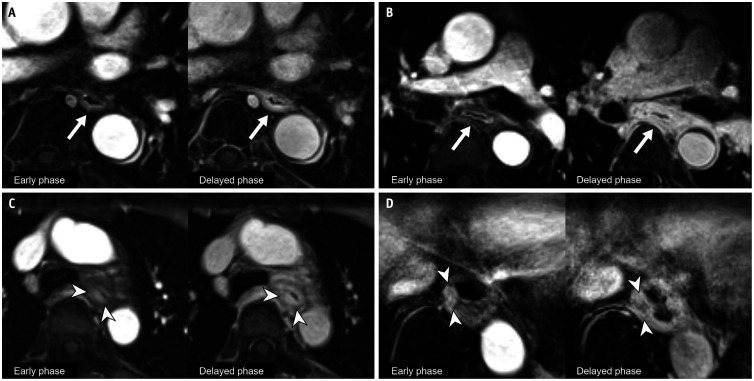

Materials and methods: Patients who underwent nCRT, subsequent MRI, positron emission tomography/computed tomography (PET/CT), endoscopy, or esophagectomy for esophageal cancer between October 2021 and October 2023 were retrospectively analyzed. The DCE-MRI response of primary tumors was interpreted using five grades by thoracic radiologists as follows: G1 (compatible with CR), G2 (probable CR), G3 (probable partial response [PR]), G4 (compatible with PR), and G5 (stable or progressive disease). The performances of MRI, PET/CT, endoscopy, and their combinations in diagnosing pCR in primary tumors were calculated.

Results: A total of 52 patients (male:female, 46:6; age, 61.2 ± 8.0 years) were included. Surgical specimens revealed pCR (ypT0) in 34 patients. G1 as the MRI criterion for pCR of primary tumors yielded a positive predictive value (PPV), specificity of 100% (18/18), and low sensitivity (23.5% [8/34]). Combining G1 and G2 as the MRI criteria increased the sensitivity to 73.5% (25/34), with a specificity of 88.9% (16/18), accuracy of 78.8% (41/52), and PPV of 92.6% (25/27). Adding the DCE-MRI results (G1-2) significantly improved accuracy for both PET/CT (from 65.4% [34/52] to 80.8% [42/52], P = 0.03) and endoscopy (from 55.8% [29/52] to 76.9% [40/52], P = 0.005), with increase in sensitivity (from 55.9% [19/34] to 82.4% [28/34] for PET/CT-based evaluation [P = 0.008] and from 47.1% [16/34] to 82.4% [28/34] for endoscopy-based evaluation [P = 0.001]).

Conclusion: DCE-MRI-based grading shows high diagnostic performance for identifying pCR in primary tumors, particularly in terms of PPV and specificity, and enhances response evaluation when combined with PET/CT and endoscopy.